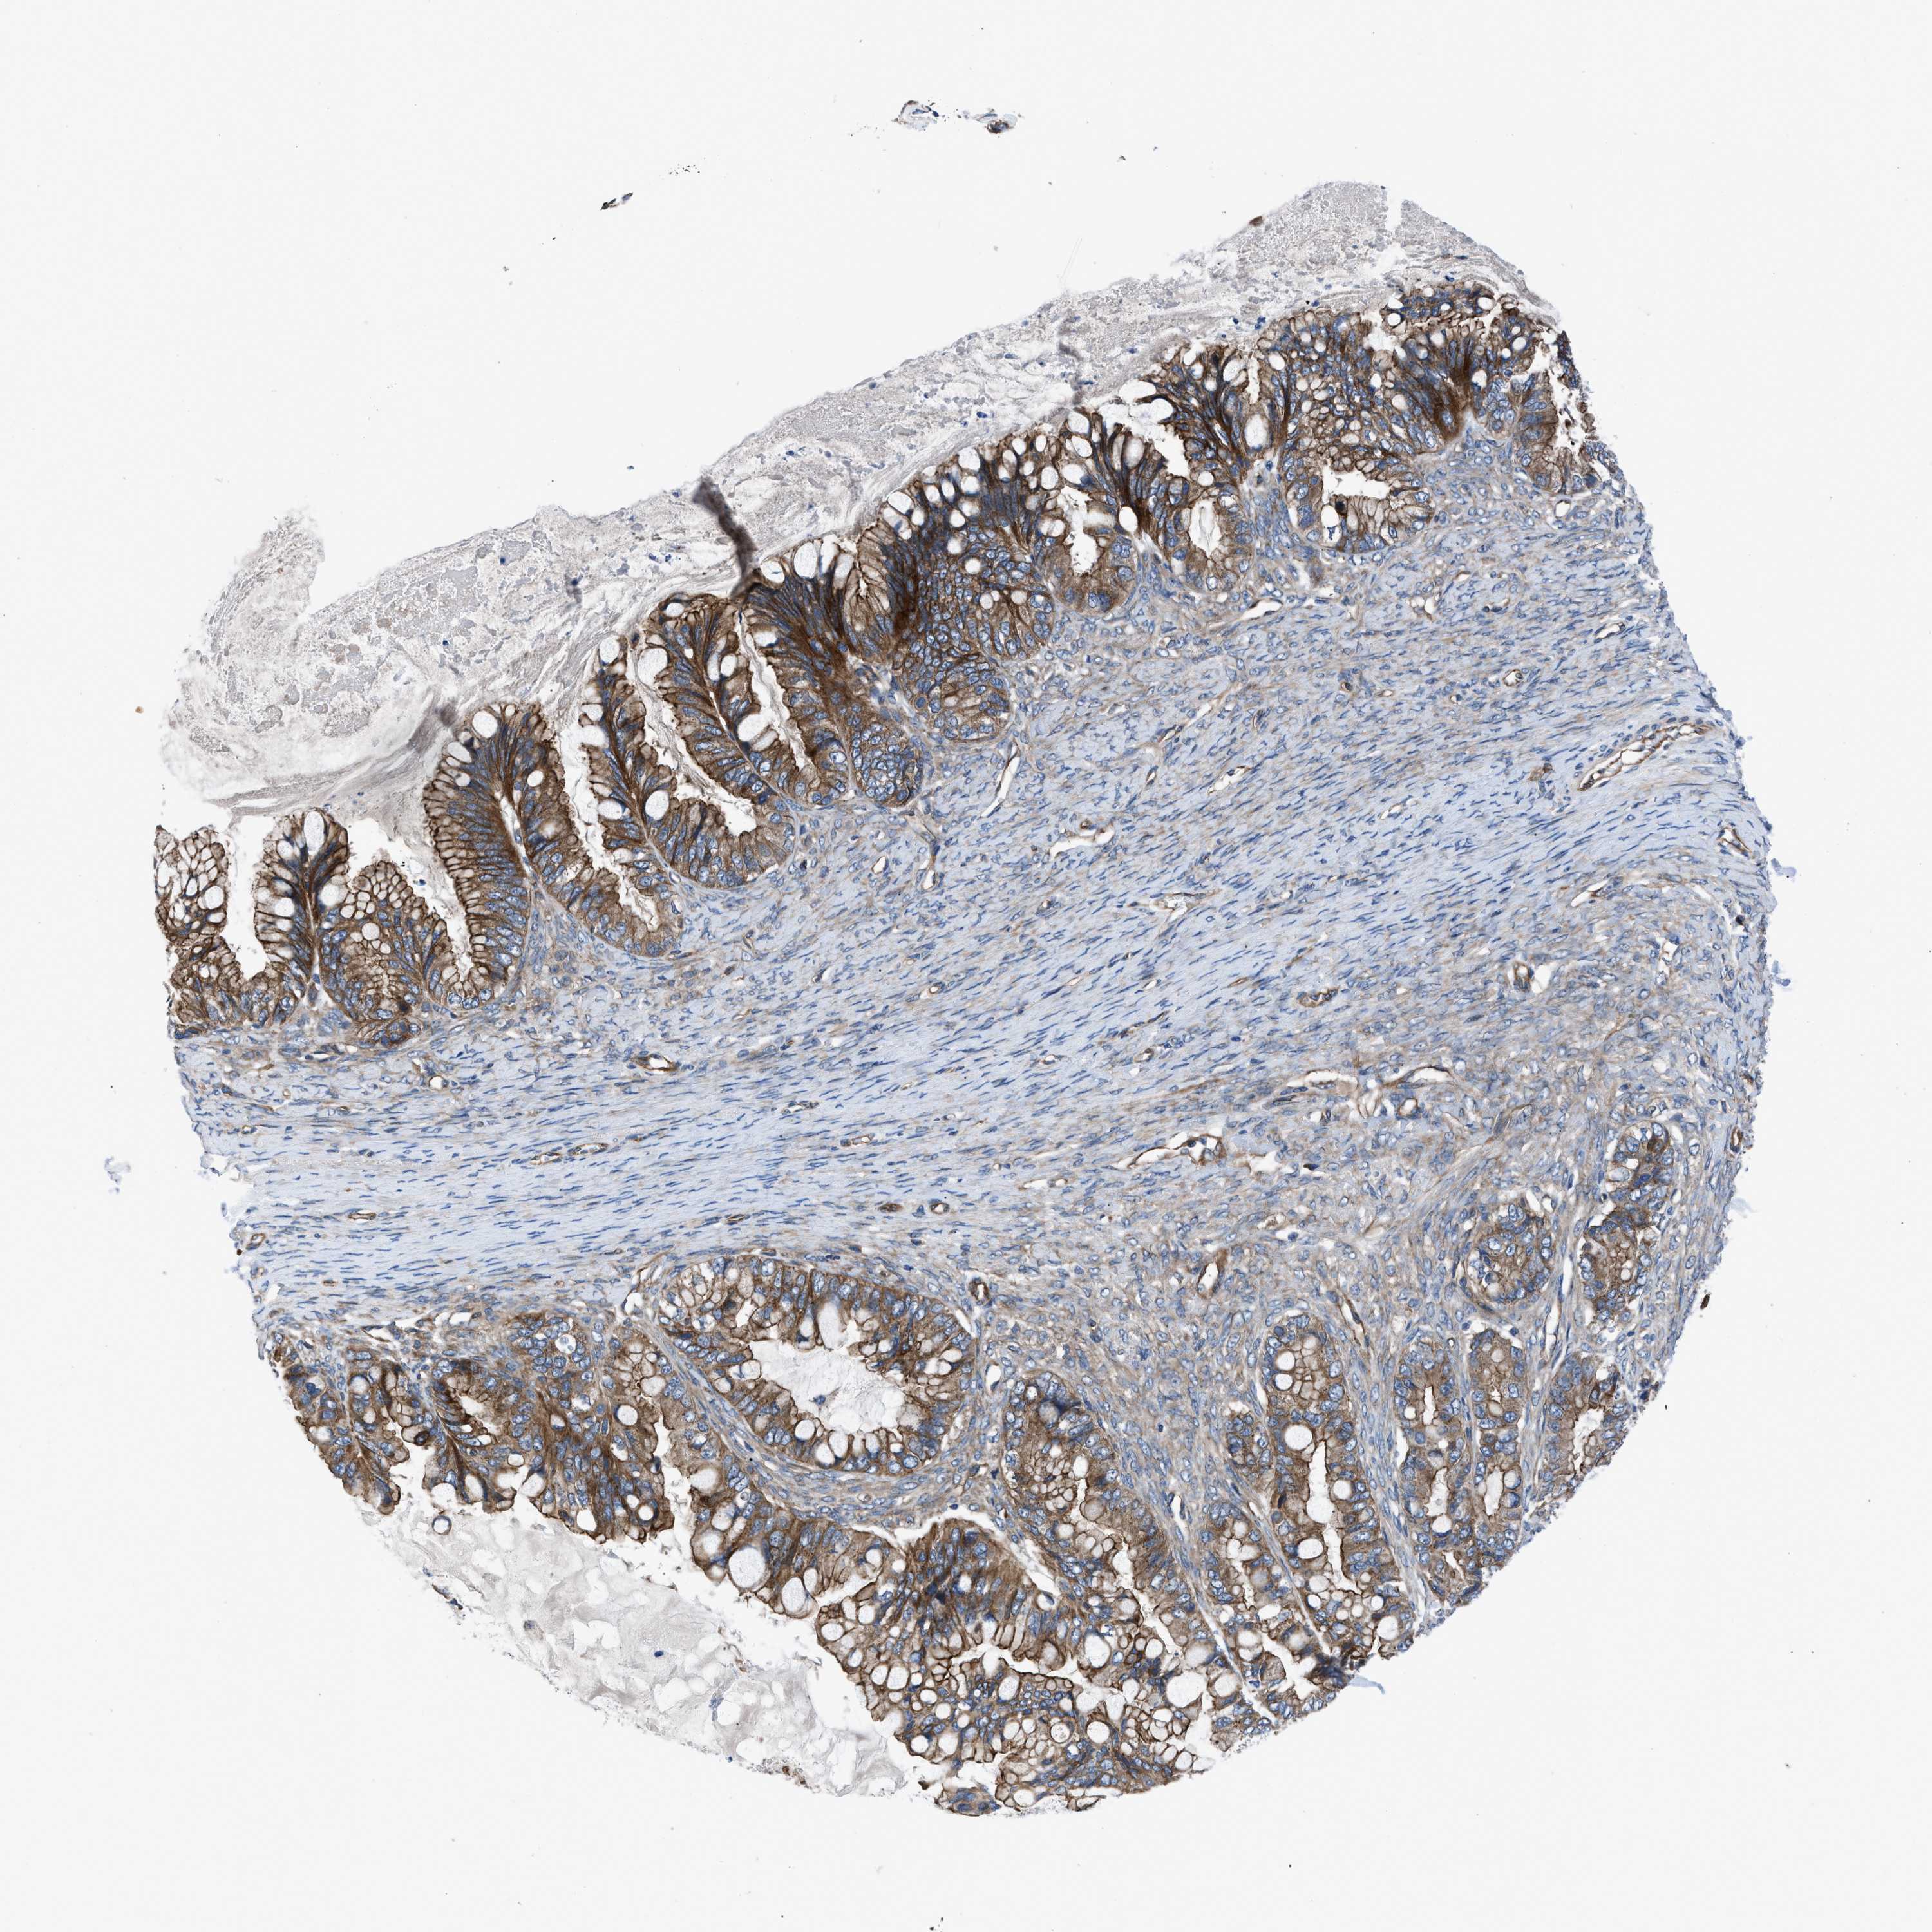

OVARIAN CANCER - Protein expressioni

A mouse-over function shows sample information and annotation data. Click on an image to view it in a full screen mode. Samples can be filtered based on level of antibody staining by selecting one or several of the following categories: high, medium, low and not detected. The assay and annotation is described here.

Note that samples used for immunohistochemistry by the Human Protein Atlas do not correspond to samples in the TCGA dataset.

Antibody stainingi

Antibody staining in the annotated cell types in the current human tissue is reported as not detected, low, medium, or high, based on conventional immunohistochemistry profiling in selected tissues. This score is based on the combination of the staining intensity and fraction of stained cells.

Each image is clickable and will lead to virtual microscopy that enables deeper exploration of all samples and also displays staining intensity scores, fraction scores and subcellular localization as well as patient and tissue information for each sample.

Antibody HPA016605

Staining

High

Medium

Low

Not detected

Intensity

Strong

Moderate

Weak

Negative

Quantity

>75%

75%-25%

<25%

None

Location

Nuclear

Cytoplasmic/membranous

Cytoplasmic/membranous,nuclear

Cystadenocarcinoma, serous, NOS

Carcinoma, endometroid

Cystadenocarcinoma, mucinous, NOS

Carcinoma, NOS